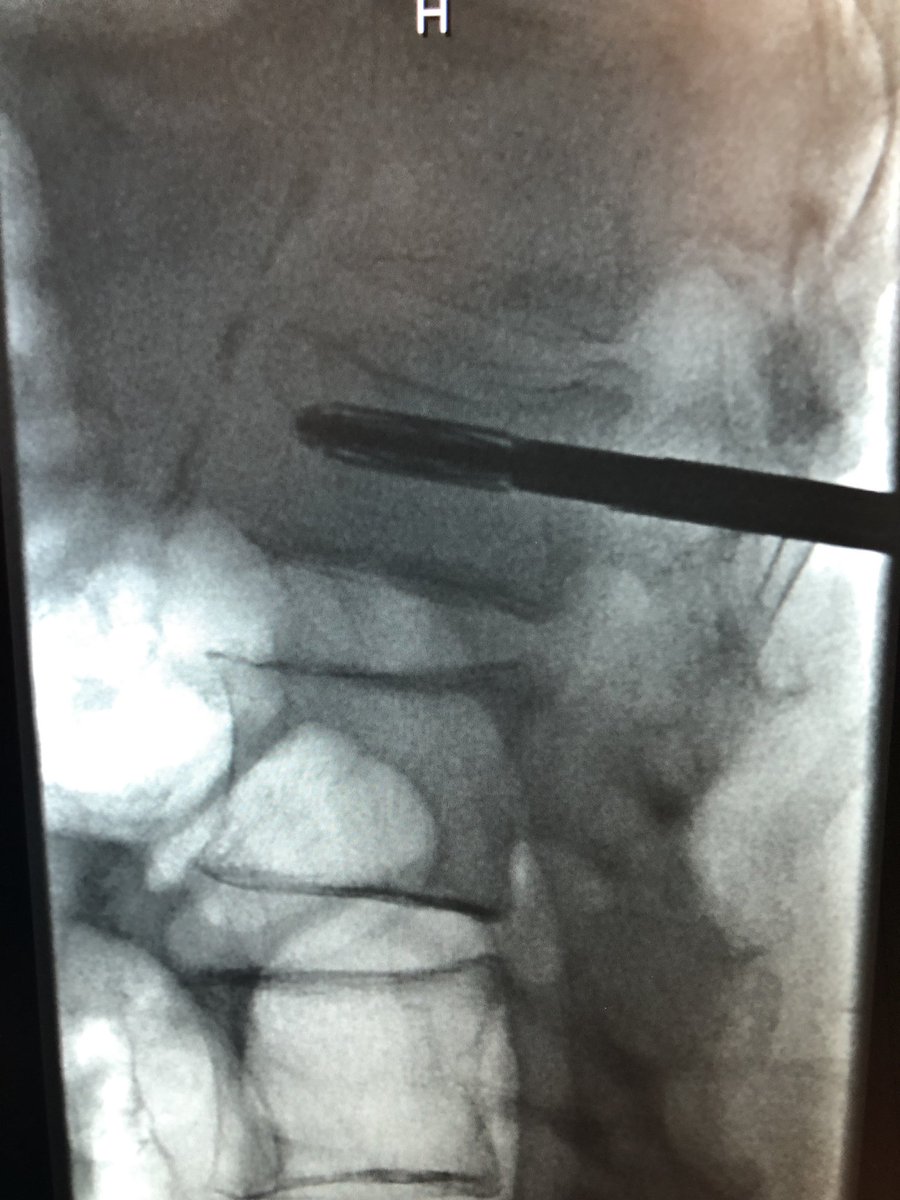

L1 vertebral Fx with nice endplate reduction and immediate pain relief.

@stryker_spine#miips#irads#SpineRad pic.twitter.com/UFXAvrI2An – mjesto: Froedtert Hospital